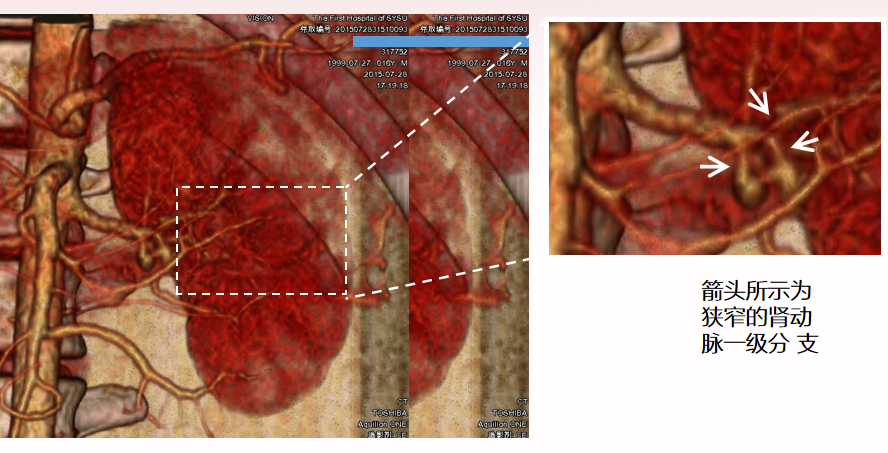

肾动脉狭窄:肾动脉重建

16岁,纤维肌性发育不良(FMD)

左肾动脉一级分支多发狭窄(3处)

左髂内动脉 Graft 重建左肾动脉,移植于左髂窝